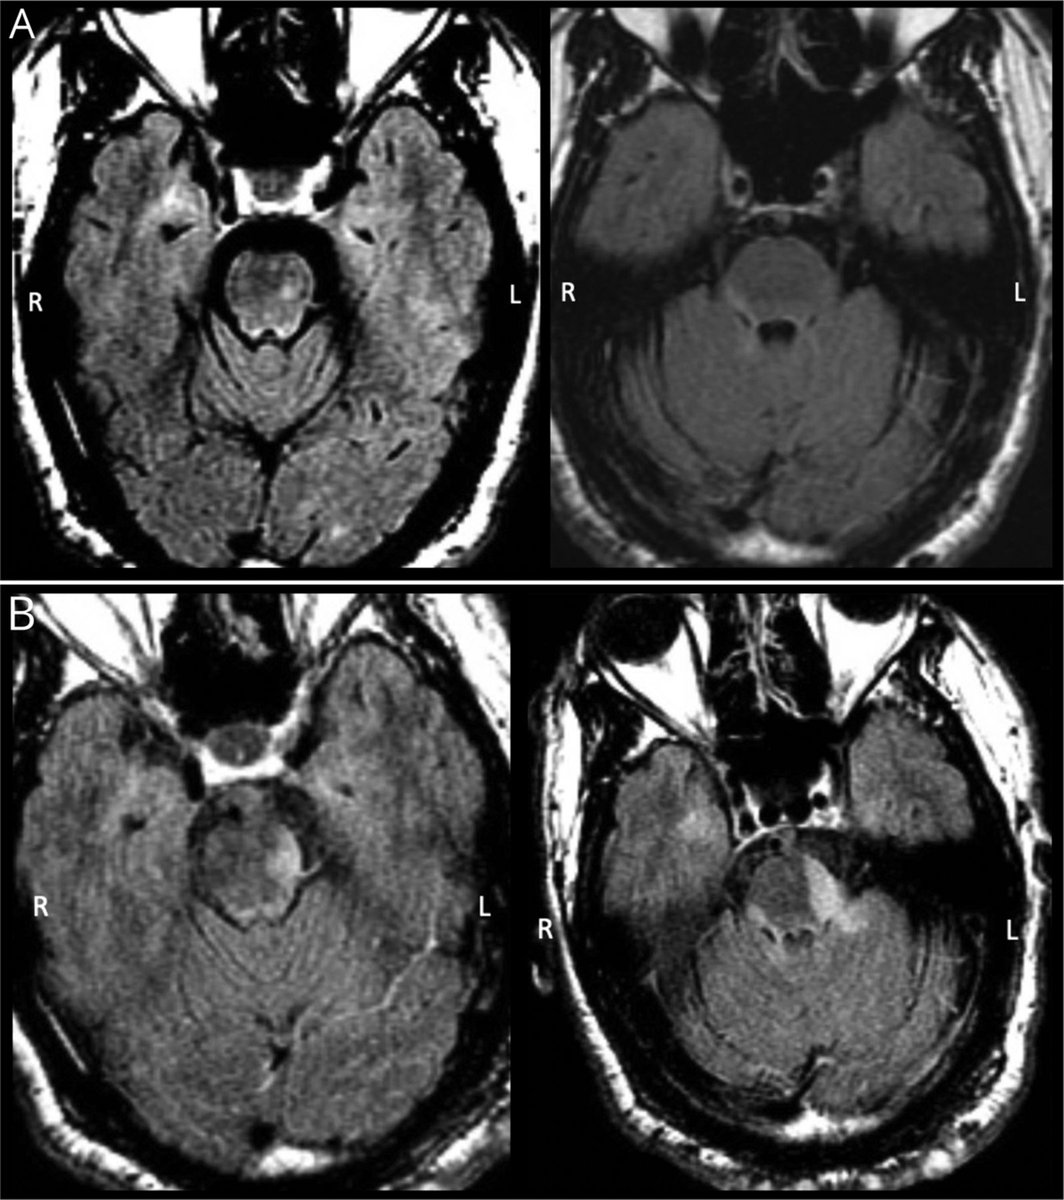

39y M #hemangioblastoma embolized with #onyx, woke up with no sensation in R face, DWI: small restricted diffusion within R superior cerebellar vermis, GTR was uneventful, extruded onyx on #trigeminal nerve & #brainstem was not removed youtu.be/s0DjD26Xkas #nsgy #microsurgery

DrBaskaya's tweet image. 39y M #hemangioblastoma embolized with #onyx, woke up with no sensation in R face, DWI: small restricted diffusion within R superior cerebellar vermis, GTR was uneventful, extruded onyx on #trigeminal nerve & #brainstem was not removed